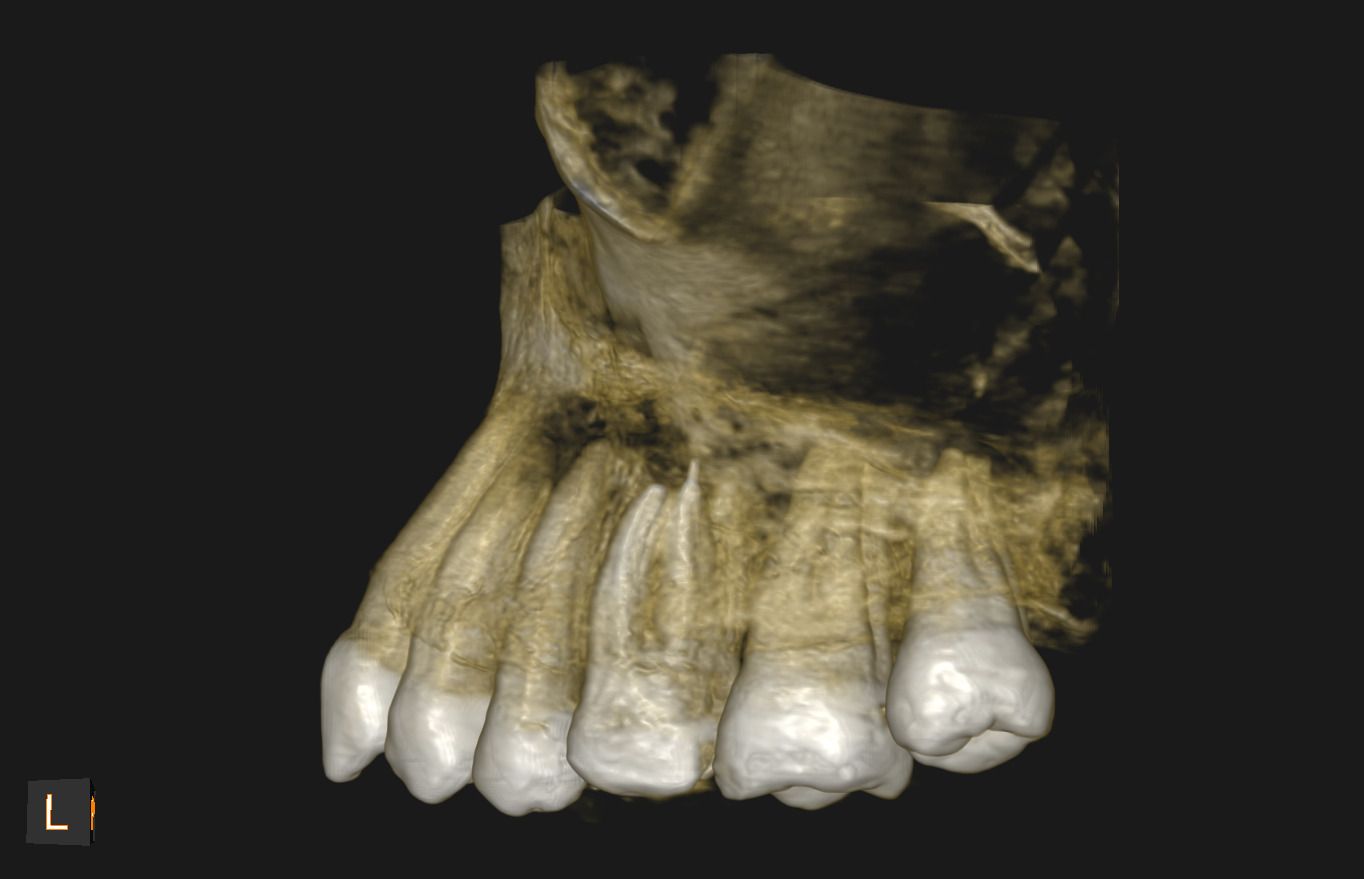

Uno de nuestros principales servicios es la adquisición de imágenes dentales 2D y 3D, fundamentales para un diagnóstico preciso y una planificación adecuada de tratamientos dentales.

Contamos con tecnología avanzada que nos permite obtener imágenes claras y detalladas de la boca y los tejidos circundantes, lo que es crucial para evaluar la salud dental y detectar posibles problemas.